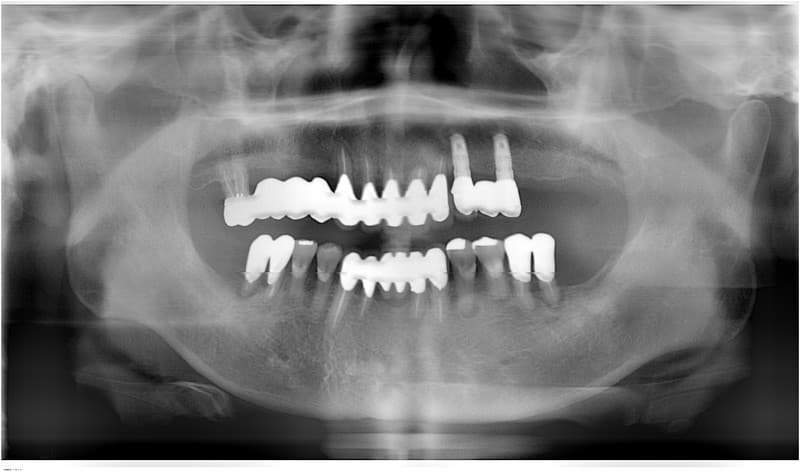

前歯部一本欠損の場合

従来の治療

両隣の健康な歯を削って土台にし、ブリッジで治療。

インプラント治療

欠損部にインプラントを埋入し、人工の歯を単独で装着。